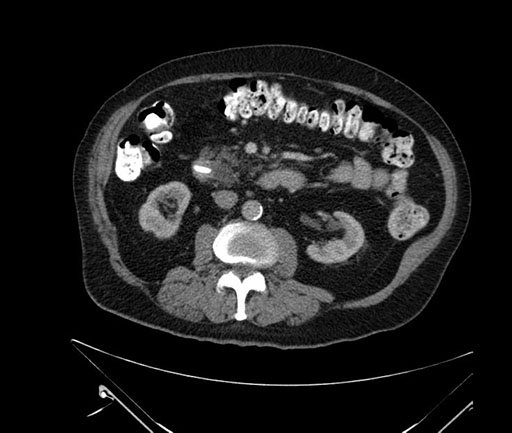

Whipple (pancreaticoduodenectomy) [case 7]

Imaging Analysis

Look through the patient's CT scan to identify any areas of concern for the necessary procedure.

Based on your CT findings, which issue(s) would give reason for "planned slowing down moment(s)" in this case?

Considering a standard Whipple procedure, what step(s) of the operation would you do differently in this case?